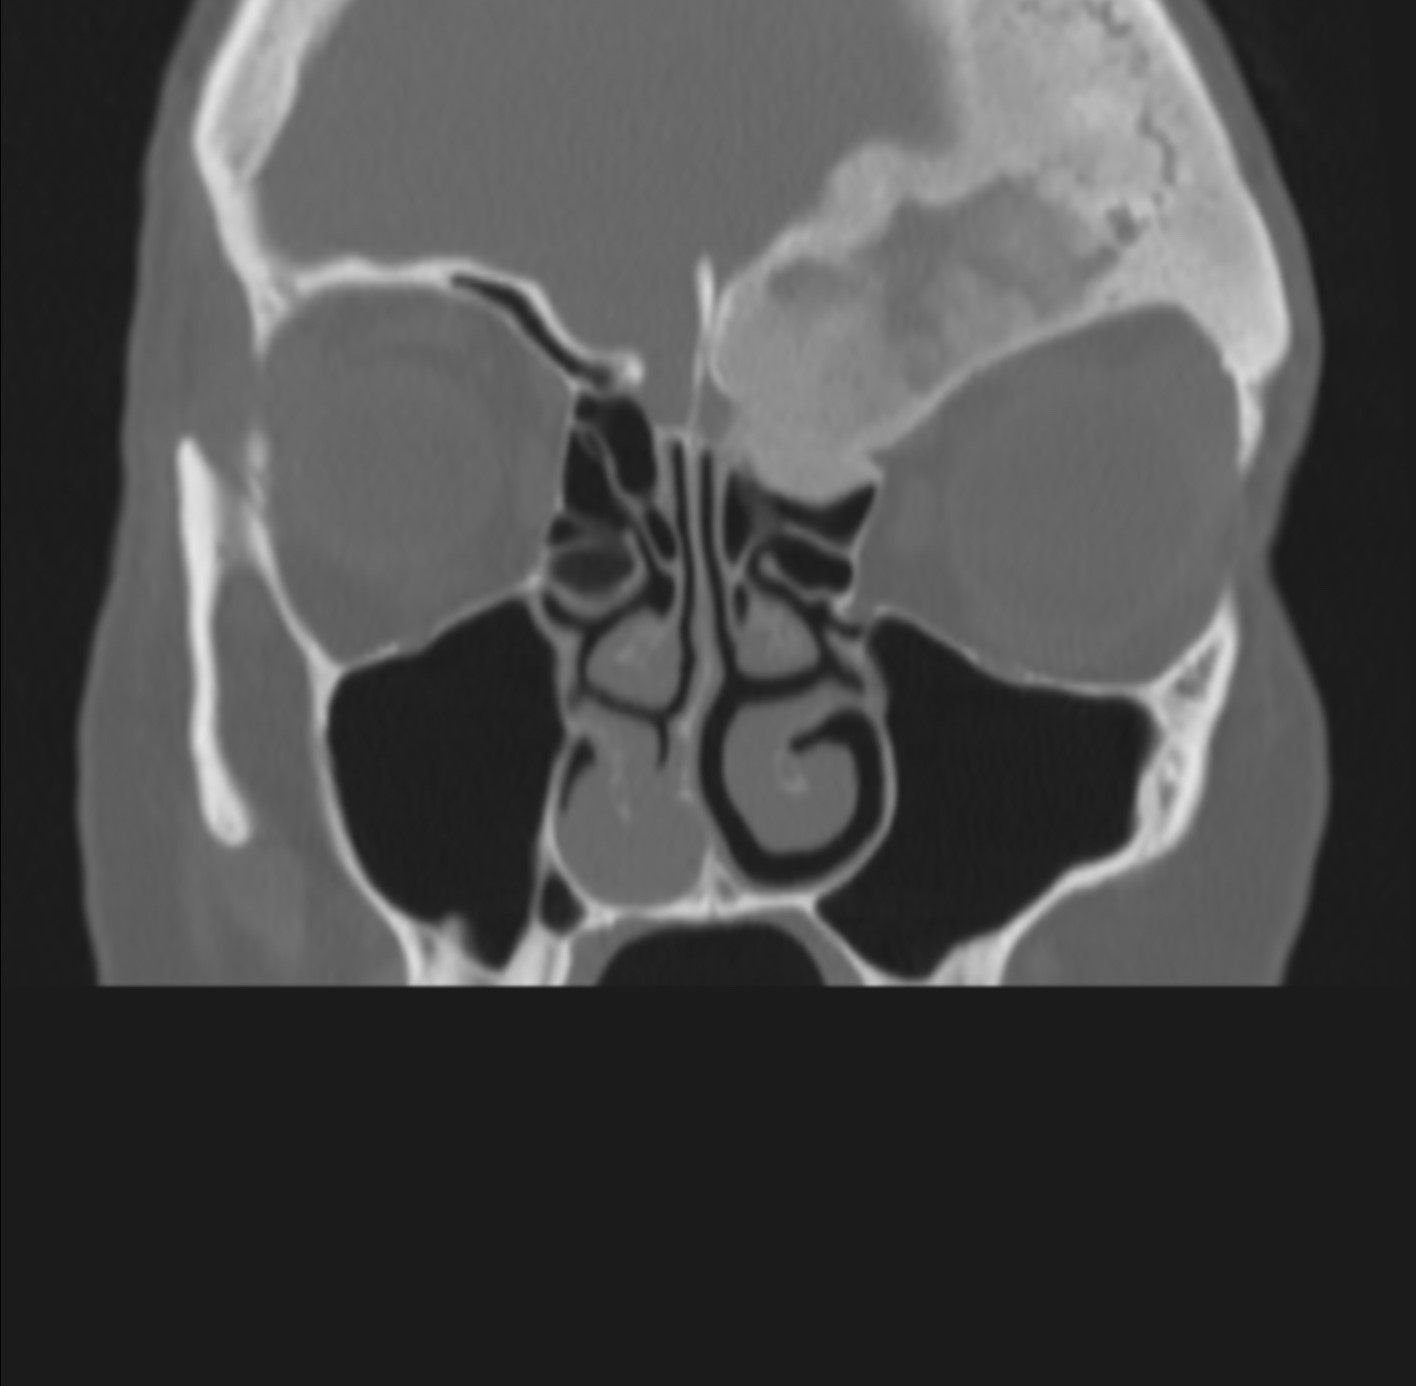

1. Resección Tumoral: Este procedimiento implica la extirpación del tumor. Los cirujanos utilizan técnicas precisas para eliminar el tumor sin dañar estructuras circundantes críticas, como nervios, vasos sanguíneos y tejidos adyacentes. (Imagen 1 y 2)

Imagen 1 y 2: Tomografía de cara. Se evidencia masa tumoral extensa con compromiso del hueso frontal y etmoides, ocasionando compresión cerebral y del globo ocular, así como asimetría facial. El tratamiento quirúrgico implicó resección tumoral y reconstrucción craneofacial con biomodelo tridimensional.